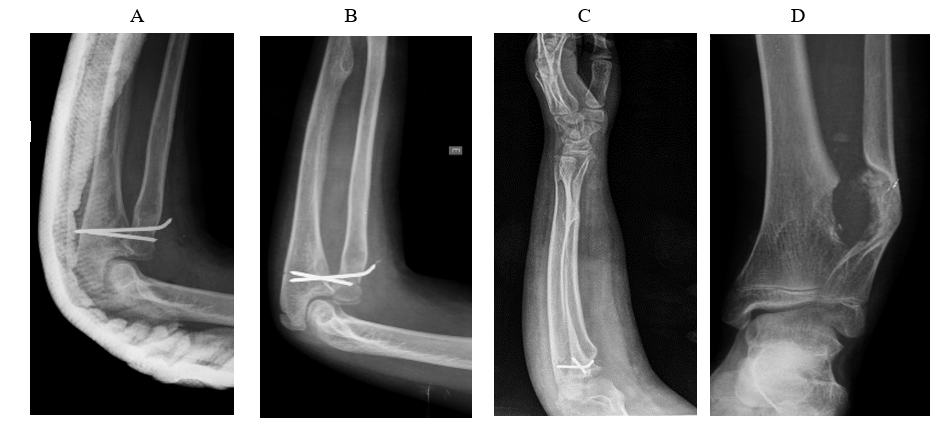

After 16 days, a new bone mass was identified, which was installed in the ulna region and associated with dislocation of the radial head referring to the left upper limb. This joint was reduced the following day (08/01/2017) and stabilized by proximal radio-ulnar fixation with two Kirschnner 2.0 wires, which prevented pronation and supination. hospital discharge on the date following this surgical procedure in good general condition and with preserved mobility of the fingers ipsilateral to the procedure. These bone masses were suspected for osteochondroma. The extracted tissue was sent to anatomopathological study after the two surgeries performed. The diagnosis of osteochondroma was confirmed and periodic control radiographs were performed postoperatively (Figure 1). In reassessment on 08/09/2017 and 08/30/2017, the patient was in good general condition and with satisfactory evolution of both surgical sites both from the clinical and radiographic point of view. Thus, we opted for follow-up after surgical resection of the osteochondroma.

Figure 1 Postoperative radiographs, demonstrating reduction and stabilization of bone structures of the radio-ulnar joint (images A, B and C) and distal third of the tibia (image D).